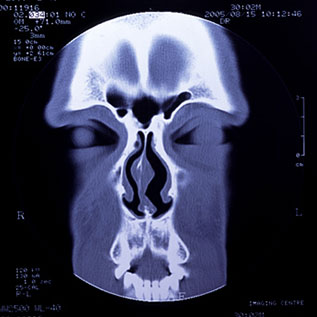

当院ではCTや内視鏡検査が可能です。

撮影した画像を用いて、わかりやすい説明を心がけます。